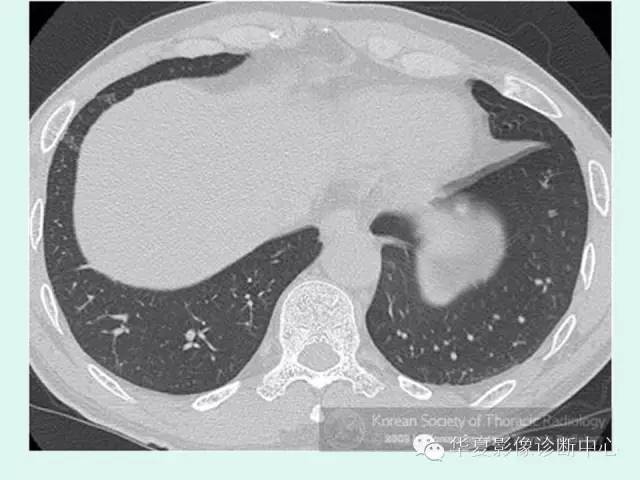

【病例】肺泡蛋白沉积症1例CT影像表现